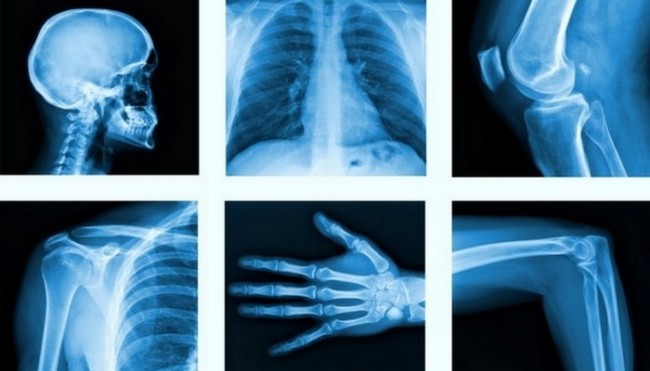

2. Рентген

Сегодня трудно представить диагностику и правильное лечение таких травм, как переломы костей, без рентгеновской технологии. Рентгеновское излучение было случайно обнаружено немецким физиком Вильгельмом Конрадом Рентгеном во время исследования прохождения электрического тока через газ с очень низким давлением.

Ученый заметил, что электронно-лучевая трубка, покрытая барийно-платиноцианидом, освещает затемненную комнату флуоресцентным светом. Так как катодные лучи были невидимы, он не знал, какие лучи дают такой свет, и стал называть их рентгеновскими лучами. За свои открытия в 1901 году ученый получил впервые в истории Нобелевскую премию по физике.